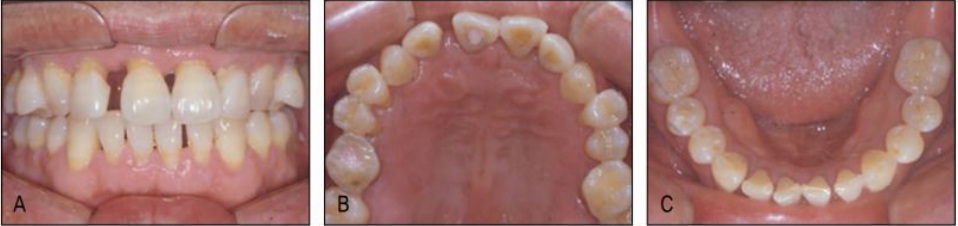

[증례] 치주질환으로 심한 병적 치아이동(pathologic tooth migration, PTM)이 나타나 기능적, 심미적 회복을 위해 교정을 한 65세 고령 환자 증례. 전악 치근단사진에서 볼 수 있듯이 전치 뿐 아니라 구치부 전 치아에 걸쳐 심한 염증이 발생하고 이로 인해 구치부에서도 PTM 이 심하게 나타나 치주치료 후 구치 교합이 불안한 상태가 초래 된 환자이었다.

치주치료 후 보철의사에게 돌아온 환자의 교합을 보고 dual bite 상태에서는 보철을 할 수 없는 바, 치주질환 이전의 교합 상태로의 교정을 의뢰하였다. 전체적으로 치주지지가 불량하여 움직일 치아만 제대로 움직 이는 치료가 매우 어려운 케이스이기 때문에 기공비용이 다소 많이 들지만 간단하게 치료 할 수 있는 투명교정장치를 사용하여 치료하기로 하였다. 구치부의 경우 협측전위된 우측 제1, 제2소구치와 좌측 제1소 구치 이동을 위해 투명교정장치를 사용할 경우 다수의 장치가 필요할 것으로 생각되어 대구치를 고정원으로 하여 소구치를 간단 하게 이동시키는 TPA 장치를 이용하였으며, 이후 투명교정장치로 전치부 공간을 클로져하여 간단하게 교정을 마무리 하였다(그 림 23-5, 6).